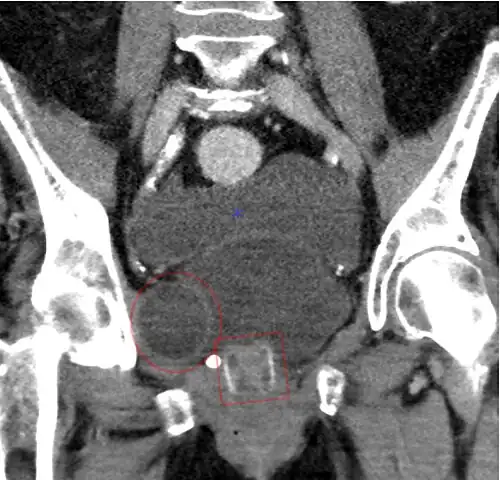

An X-ray image of implanted ZSI 375. The device is deactivated – the spring is compressed below the top of the cylinder. Patient is incontinent. -

An X-ray image of implanted ZSI 375. The device is activated – the spring is decompressed at the top of the cylinder. Patient is continent. -